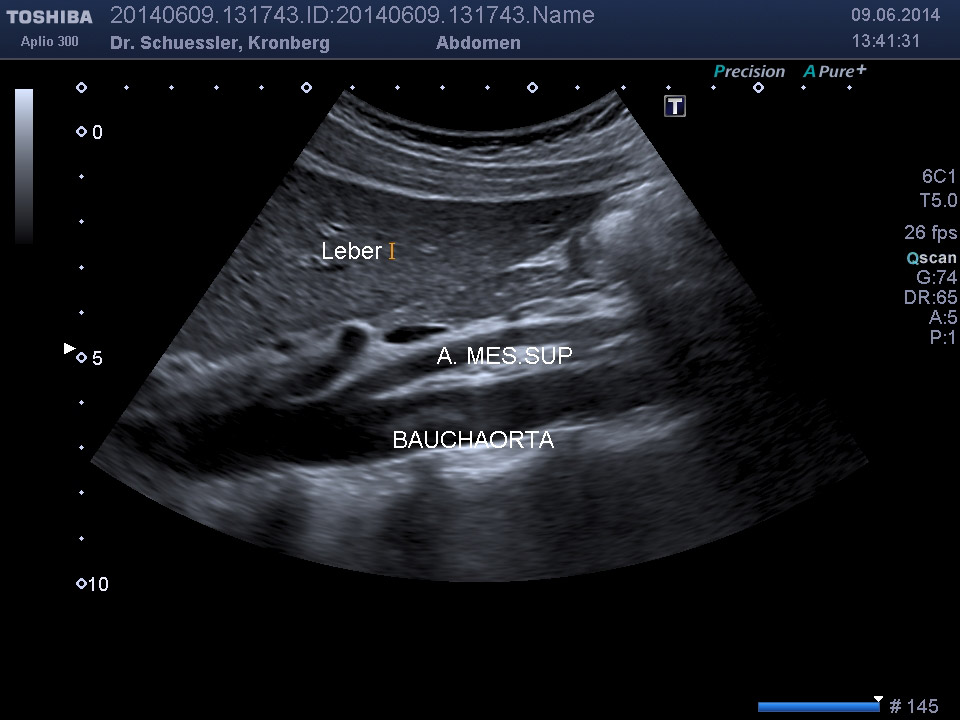

Die Bauchultraschalluntersuchung ist das wichtigste Verfahren zur Beurteilung der gesamten Bauchorgane. Sämtliche Bauchorgane sind dem Ultraschallverfahren ohne Belastung für den Patienten gut zugängig.

Durch Ergänzung des farbkodierten Duplexverfahrens läßt sich die Durchblutungssituation der Bauchorgane erfassen.